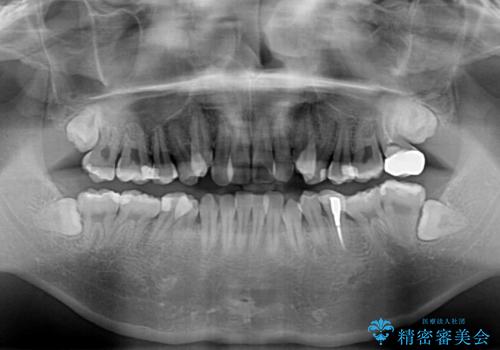

診査の結果、上下前歯に強い叢生が認められ、歯をきれいに並べるためのスペースが明らかに不足していました。

無理に歯を並べると、前歯が前方に突出するため、抜歯によるスペース確保が必要と判断しました。

上下左右の小臼歯を抜歯し、歯列を整えるためのスペースを確保

左下は第二小臼歯に根管治療歴があったため、左下のみ第二小臼歯を抜歯しアンカースクリューを併用

それ以外の部位は第一小臼歯を抜歯